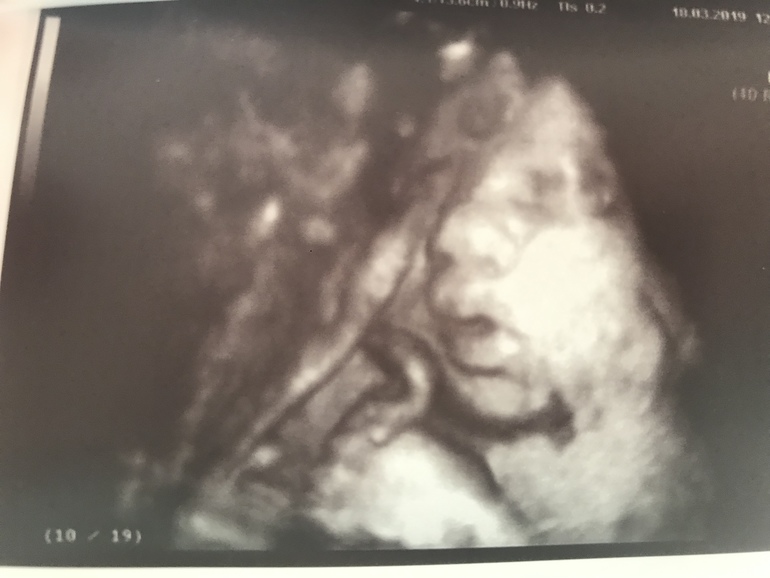

Завтра 32недели ровно

Вес 1901гр😍

Все органы функционируют хорошо, кровотоки хорошие, мой шов просто замечательный😎

Он много раз сказал, что это папина дочка (ресницы длинные, губы пухлые, головка большая)❤️ А волосы в маму «будет светлая шатенка, волосы кудрявенькие»😁

Пальчик сосала, потом губы трубочкой сложила, а он говорит «она плюётся!🤦🏻♀️😁 кто у тебя из сыновей ещё плюётся?». Я так подумала и отвечаю «средний», а он «так у тебя дети через одного плюются!»🙈😂

Спросил, как назвала. Я ответила «Арина», а он «не Родионовна?», я «нет, Валентиновна» - и она в этот момент улыбнулась 😊😍

Всё УЗИ была серьёзная, а тут улыбнулась... Моя принцесса 👑, моё солнышко ❤️